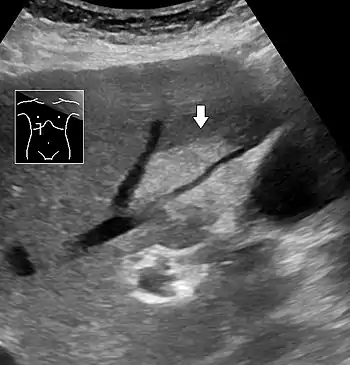

On X-ray computed tomography (CT), the increased fat component will decrease the density of the liver tissue, making the image less bright. Typically the density of the spleen and liver are roughly equivalent. In steatosis, there is a difference between the density and brightness of the two organs, with the liver appearing darker.[12] On ultrasound, fat is more echogenic (capable of reflecting sound waves). The combination of liver steatosis being dark on CT and bright on ultrasound is sometimes known as the flip flop sign.

On abdominal ultrasonography, steatosis is seen as a hyperechoic liver as compared to the normal kidney.